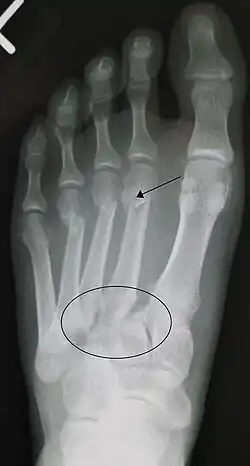

![]() Fractura de lisfranc, marcada con el círculo. Además, fractura a nivel distal del 2º (marcada con una flecha), 3º y 4º metatarsianos. | ||

La lesión de Lisfranc hace referencia a la fractura, luxación o esguince que se produce en la articulación tarso-metatarsiana (también denominada, articulación de Lisfranc). La lesión tiene un carácter de mayor severidad debido al compromiso total o parcial que puede tener el ligamento de Lisfranc, lo cual produce una gran inestabilidad a nivel de la articulación.

El diagnóstico se basa en la imagenología y la clínica, esta última se puede presentar con las características clásicas de una fractura (dolor, aumento de volumen e impotencia funcional) en la región media del pie, sumada a una equimosis en la región del arco plantar. La valoración radiográfica de las relaciones normales del complejo tarsometatarsiano se lleva a cabo en las proyecciones Dorsoplantar en la que la cortical medial de la cuña intermedia, se continua con la cortical medial de la base del 2º metatarsiano. En la proyección oblicua lateral: la cortical medial del cuboides se continua con la cortical medial de la base del 4º metatarsiano en las placas simples y de estrés.